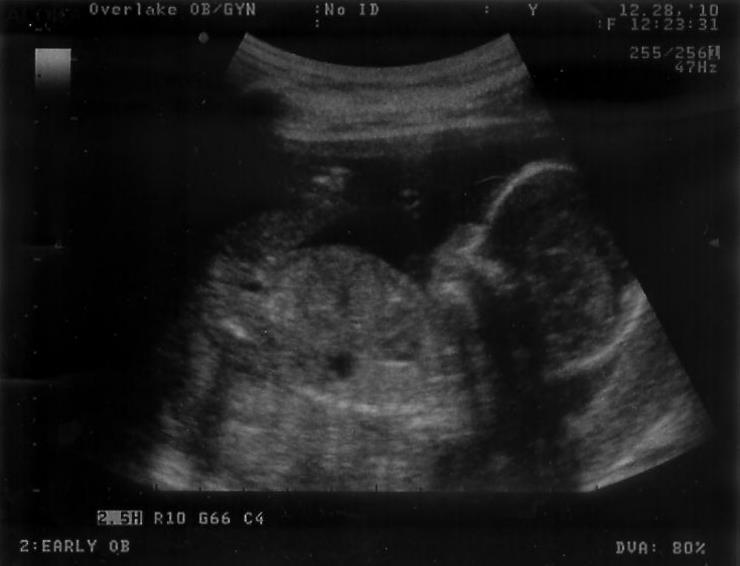

Today we went in for our routine monthly appointment. Since our doctor was booked full, we met with a midwife/nurse practitioner instead. All we had scheduled was a check of the baby's heartbeat, which was normal at 150 BPM. But, our midwife was really nice, and asked if we wanted to see the baby really quickly. I think she enjoyed doing ultrasounds, because we had a fun time of it. The first shot we got was a nice side profile:

Our second ultrasound on December 28th, 2010.

The baby was sleeping, and his arm was resting behind his head, much as his mother rests! The midwife prodded Olivia's stomach with the ultrasound head, and the baby woke up! He was opening and closing his mouth, and flailing his legs a bit. Apparently all the amniotic fluid gave him the hiccups, and we could see him go through the motions just like a big person. After being woken up, he turned his body toward the ultrasound, tucked up his knees in front of his body, and we couldn't see much more. It was great to see our baby when he looks more human and less alien, and the 20 week ultrasound we'll be getting in a month will look even better.